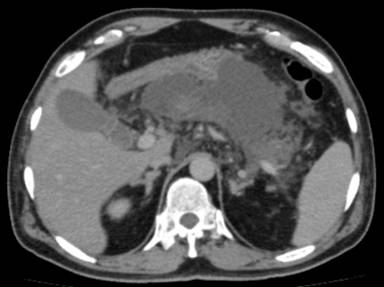

He was admitted into the intensive care unit, his oral hypoglycemic agents were discontinued and was initiated on insulin. A repeat CECT abdomen on the fifth day showed extensive pancreatic and peripancreatic necrosis (Figure 2). His hospital stay was complicated by worsening jaundice, a magnetic resonance cholangiopancreatography showed necrotic debris compressing on the common bile duct (Figure 3). He underwent a laparoscopic pancreatic necrosectomy with a laparoscopic cholecystectomy and placement of a feeding jejunostomy tube. Intra-operatively the gallbladder was found to be gangrenous with a friable biliary tract, and there was an avulsion of the cystic duct. On the ninth post-operative day he underwent an ERCP and stenting of the common bile duct. Further, his hospital course was complicated by methicillin resistant Staphylococcus Aureus infection in the central venous catheter which was treated with intravenous vancomycin. He was discharged from the hospital on the fiftieth day of hospital stay in a stable state. On follow up for 9 months post discharge, and on insulin for his diabetes, our patient is healthy and asymptomatic.

Figure 2. CECT abdomen on day 5 showing pancreatic and peripancreatic necrosis. |